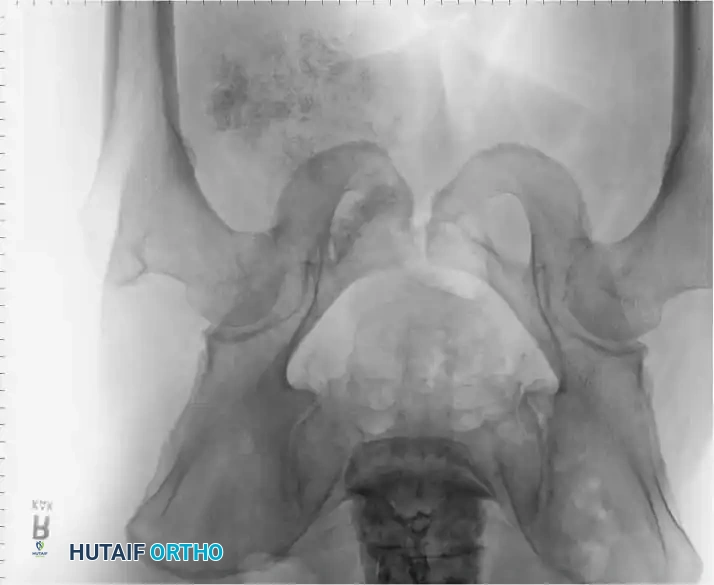

Intraoperative Imaging and Margin Assessment

Continuous intraoperative assessment using fluoroscopy and frozen section pathology is mandatory. The following images demonstrate various stages of complex upper extremity resections, allograft preparations, and prosthetic implantations across the humerus and elbow joint.